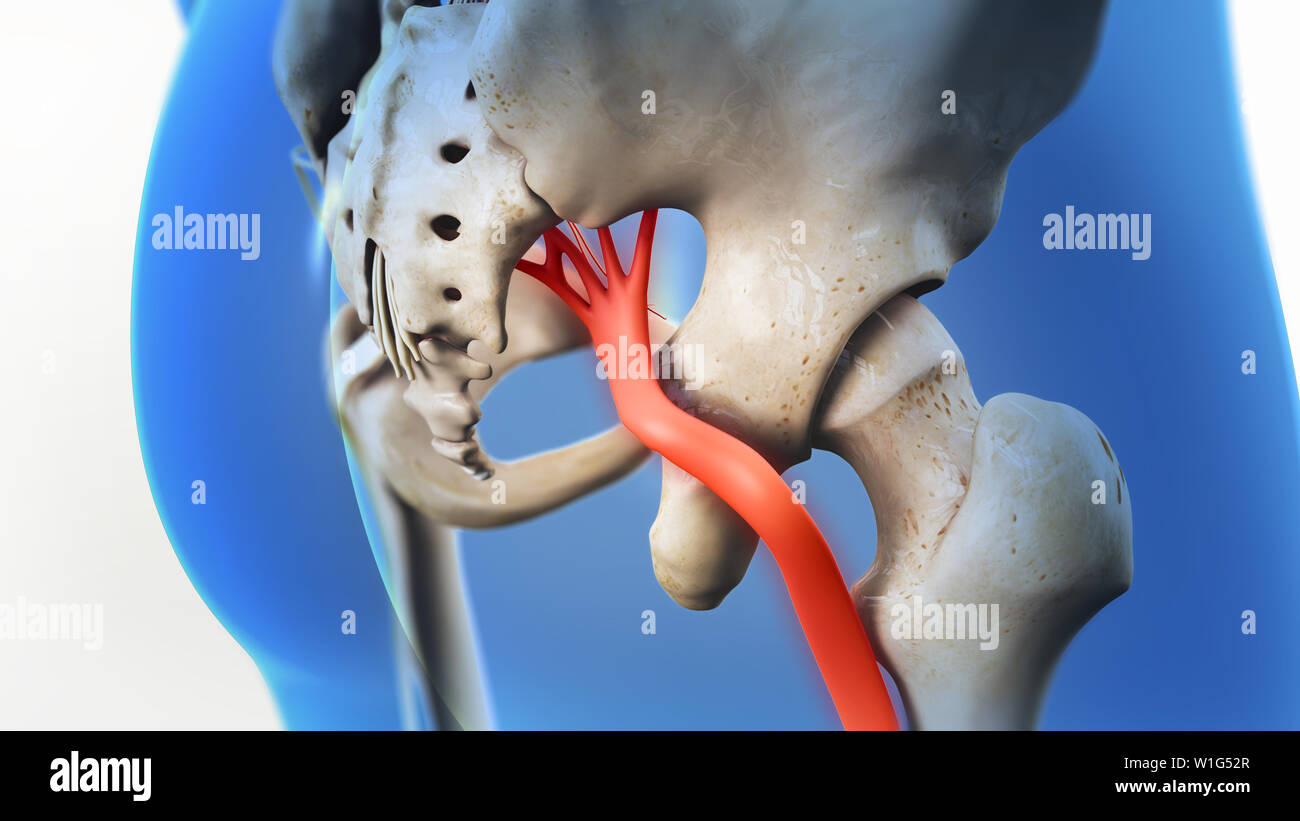

La douleur du nerf sciatique 3D Illustration Banque D'Imageshttps://www.alamyimages.fr/image-license-details/?v=1https://www.alamyimages.fr/la-douleur-du-nerf-sciatique-3d-illustration-image259125407.html

La douleur du nerf sciatique 3D Illustration Banque D'Imageshttps://www.alamyimages.fr/image-license-details/?v=1https://www.alamyimages.fr/la-douleur-du-nerf-sciatique-3d-illustration-image259125407.htmlRFW1G52R–La douleur du nerf sciatique 3D Illustration